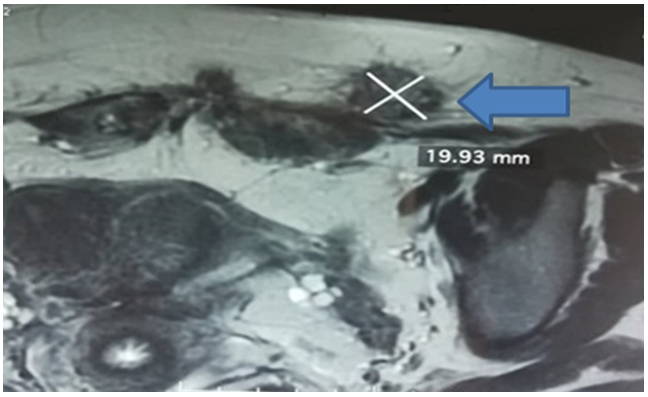

Diagnostic approach: Soft tissue ultrasound found an 18 mm heterogeneous hypoechoic lesion, located opposite the left side of the pelvic scar. Abdominopelvic computed tomography (CT) found a 3cm oblong mass, adherent to the left rectus muscle and its fascia, hypodense and poorly limited (Figure 1A, Figure 1B). Biopsies were not taken. The diagnosis of endometriosis was strongly suggested by this set of anamnestic, clinical and para-clinical arguments and the decision was made to operate on the patient.

Figure 1: Abdominopelvic CT scan: parietal lesion in the rectus muscle: (A) sagittal section, (B) axial section